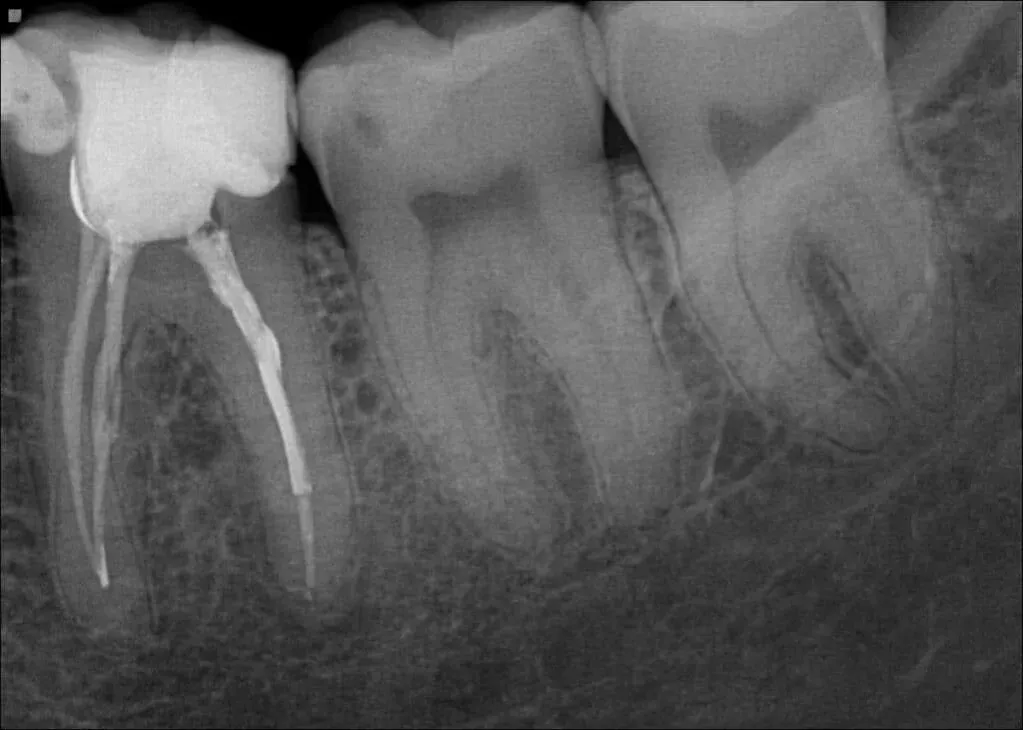

Jako stomatolog, często polegam na zdjęciach rentgenowskich (RTG), by ocenić stan korzeni zębów, które są przecież niewidoczne gołym okiem. Na takim zdjęciu zdrowy korzeń zęba powinien mieć gładkie, wyraźnie zarysowane kontury i jednolitą strukturę. Jego wierzchołek, czyli sam koniec, powinien być wyraźnie zamknięty, co świadczy o prawidłowym rozwoju i braku procesów zapalnych w tej okolicy.

Równie ważne jest to, co otacza korzeń. Zdrowa kość, czyli zębodół, powinna być gęsta i ściśle przylegać do korzenia. Pomiędzy kością a korzeniem widoczna jest cienka, ciemniejsza linia to przestrzeń ozębnej, która zawiera więzadła utrzymujące ząb w zębodole. Jej równa szerokość i ciągłość są kluczowymi wskaźnikami zdrowia. Jakakolwiek zmiana w tych strukturach może sygnalizować początek problemów, dlatego tak ważne jest regularne wykonywanie zdjęć RTG, zwłaszcza podczas kontrolnych wizyt.

Niestety, korzenie zębów nie zawsze są w idealnym stanie. Istnieje wiele problemów, które mogą je dotknąć, a ich wczesne rozpoznanie jest kluczowe dla skutecznego leczenia. Jednym z najczęstszych sygnałów alarmowych na zdjęciu RTG jest ciemna plama lub przejaśnienie wokół wierzchołka korzenia. To zazwyczaj wskaźnik zapalenia tkanek okołowierzchołkowych, co oznacza zanik kości spowodowany infekcją bakteryjną. Najczęstszymi przyczynami są nieleczona, głęboka próchnica, która dotarła do miazgi, lub powikłania po wcześniejszym leczeniu kanałowym. Taki obraz wymaga natychmiastowej interwencji.

Jednym z najbardziej bolesnych i niebezpiecznych stanów jest ropień okołowierzchołkowy. Na zdjęciu RTG widoczny jest jako wyraźnie odgraniczone, okrągłe, ciemne pole przy wierzchołku korzenia. To znak, że infekcja bakteryjna rozprzestrzeniła się poza ząb, tworząc zbiornik ropy. Objawy alarmowe są zazwyczaj bardzo wyraźne: silny, pulsujący ból, opuchlizna twarzy lub dziąsła, a niekiedy nawet gorączka. W takiej sytuacji natychmiastowa wizyta u stomatologa jest absolutnie konieczna, aby zapobiec dalszemu rozprzestrzenianiu się infekcji.